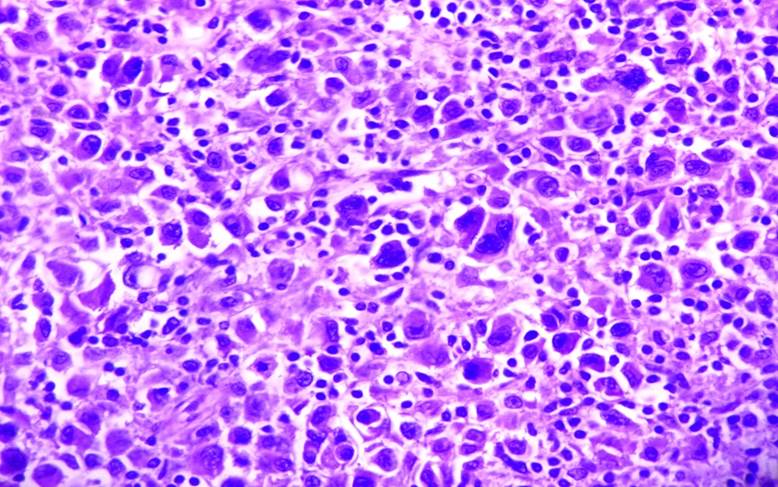

Reporte histopatológico: Melanoma nodular, multicéntrico, ulcerado, con infiltración a cuerpo esponjoso (2.5cm de profundidad). Borde distal y marginal libre de lesión. Breslow 25 mm, 1 mitosis/mm2 (Fig. 4 y 5)

Figura 4 Microfotografía 40x. Numerosas células melanocíticas atípicas con grandes núcleos hipercromáticos, eosinófilo y abundante citoplasma.